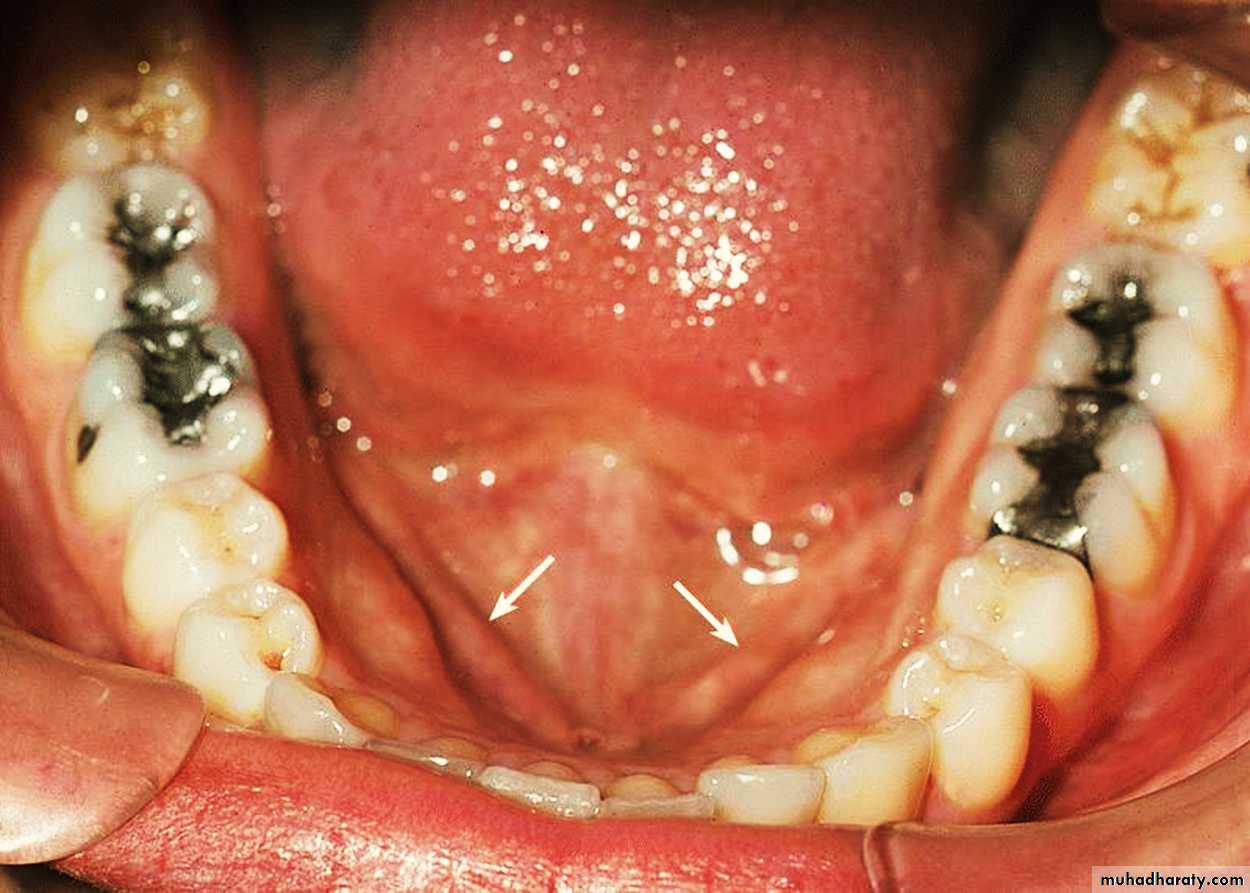

The ventral surface (underside) is stratified squamous non-keratinized epithelium which is smooth.Sublingual Region

1- Frenulum of tongue.2- Sublingual fold.

3- Sublingual papilla.

4- Opening of submandibular duct